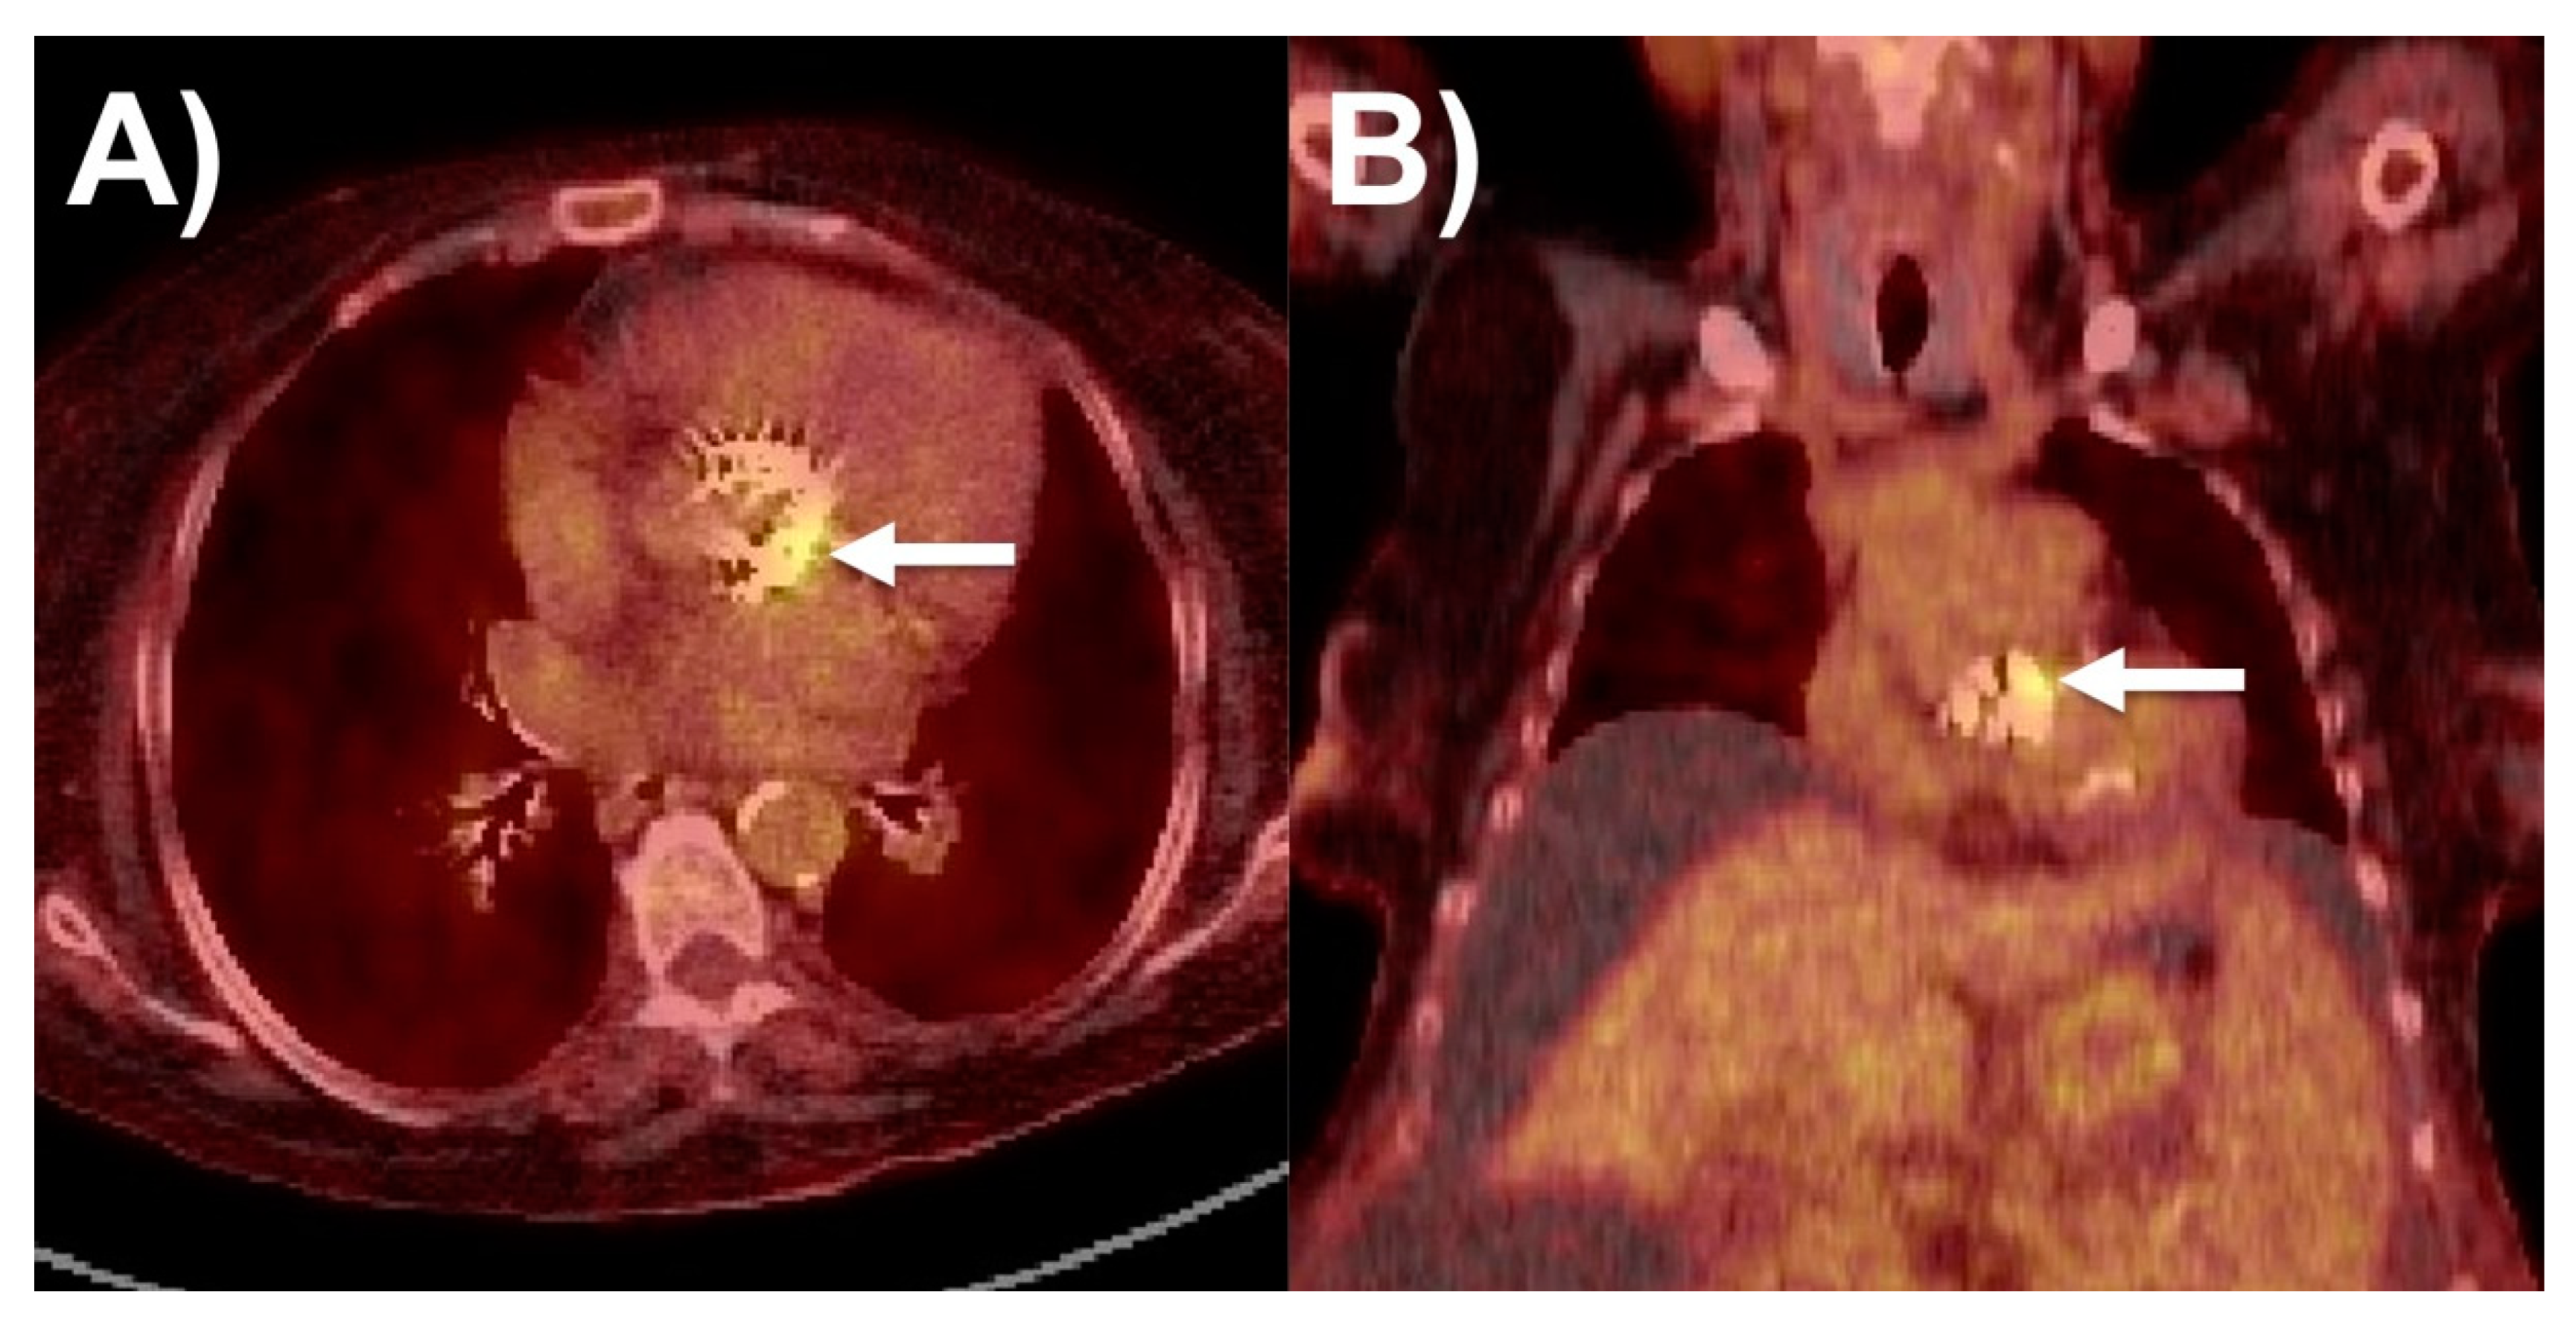

6.1. 18F-FDG PET/CT

| 18F-fluorodeoxyglucose positron emission tomography/computed tomography (18F-FDG PET/CT) | Improved sensitivity for prosthetic valve and device-related endocarditis in some scenarios. | Non-portable, low sensitivity for native valve endocarditis, no functional cine imaging, radiation exposure, special pre-test preparation, cost, false-positive results within 3 months after cardiac surgery, false-negative results in patients treated with antimicrobials. |